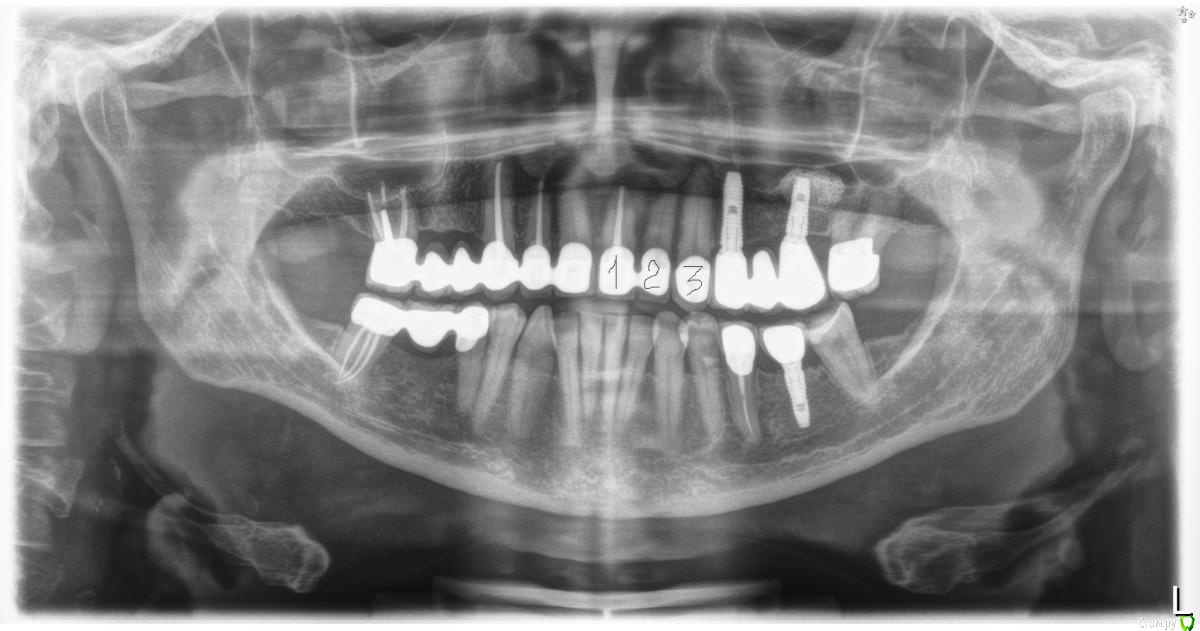

ellenchik Опубликовано 31 октября, 2017 Поделиться Опубликовано 31 октября, 2017 Уважаемые Стоматологи, Год с небольшим назад протезировала зубы в клинике в Венгрии. Летом начал болеть верхний левый передний зуб под коронкой. Реагировал на холодное, ноющая боль периодически. На очном приеме стоматолог (протезировал не он) по снимку и по пробам азотом,перкуссии ничего не находил. Сказал, ждать-наблюдать. Нерв живой,возможно всё стабилизируется. Но боль повторялась периодически. ( Чистила спец.пастой для особо чувствительных зубов, принимала ибупрофен) В сентябре на приеме тоже самое, врач не видит причины ни по снимку, ни при осмотре) Неделю назад пришла к врачу с этой же проблемой. Ноет, болит зуб под коронкой. Посмотрел зуб, проба азотом, простучал этот зуб и соседние. Надкусывание тоже безболезненное. Снимок не стал делать, сказал,слишком часто не надо. Но вот 3 дня назад я откусила булочку и на этот зуб попал тведый орешек. Через час зуб разболелся прилично и болит уже 3 дня. Боль нерезкая,ноющая, жгучая, будто заноза внутри . . Завтра иду на прием. ( я сейчас в Германии ). У меня несколько вопросов : 1. Можно ли провести еще какую-либо диагностику?2. При необходимости лечения - возможно ли провести его через коронку? Или ...?3. Можно ли что-то сказать по снимкам ? Общая рентгенопанорама - июль 2017 . Зуб уже болел.Прицельный снимок - сентябрь/ Проблемный зуб отмечен кружочком. Заранее спасибо. Ссылка на комментарий

ellenchik Опубликовано 3 мая, 2018 Автор Поделиться Опубликовано 3 мая, 2018 Уважаемые Доктора! Я снова к Вам с просьбой. Продолжу мою тему.После депульпирования 21 зуба, боль в области трех обозначенных на снимке верхних передних зубов осталась прежней. Появляется спонтанно в любое время. На перкуссию - спокойно. Боль жгучая,ноющая,разлитая.Иногда отдает в переносицу. Врач говорит,возможно у зуба № 2 большая пломба давит на нерв. Я ощущаю часто боль в зубе № 3. Несколько дней может быть всё спокойно. Принимаю Ибупрофен 400. Иногда помогает иногда нет. Ощущение,что болят эти 3 зуба. Конкретно уже не могу сказать. Будучи проездом в Питере ,сделала 3 Д томографию,но только диск без описания, к врачу не попала, к сожалению. Здесь врач (в Германии в маленьком городке ) с этим не работает. Посмотрите ,пожалуйста, общий срез-снимок. Зубы 1-2-3. Номер 1 депульпирован в январе, как предполагаемый источник проблемы и боли. Подскажите,пожалуйста, какие срезы сделать и выложить для бОльшей информативности. Очень надеюсь на Вашу помощь. Спасибо всем откликнувшимся. С уважением Елена Ссылка на комментарий